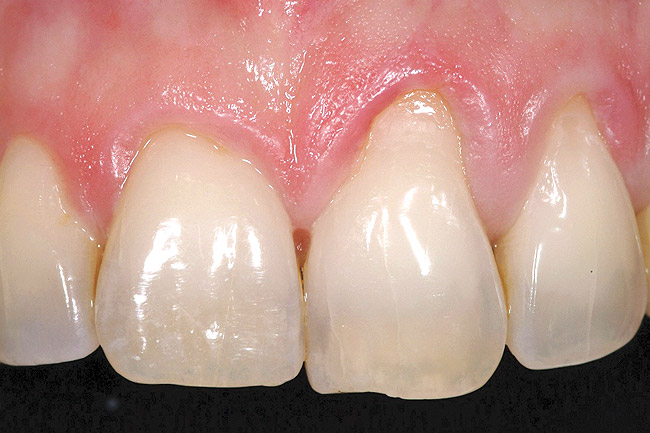

The 2.5-week postoperative clinical view can be seen in Figure 10 through Figure 12. Note the rapid soft tissue healing and maturation. At 6-weeks postoperative, tissue plasty was accomplished to blend the thickened keratinized tissue, in addition to placement of class V composite restorations at teeth Nos. 5, 6, and 11 to create a new restorative margin on the root surfaces.

The 2-month postoperative view can be seen in Figure 13 through 15. Note the color match of the tissue, balance of the facial heights of contour, and zones of attached keratinized tissue present.

Figure 10  Case One The 2.5-week postoperative view, maxillary anterior.

Figure 10

Figure 14  Case One The 2-month postoperative view, maxillary anterior.

Figure 14